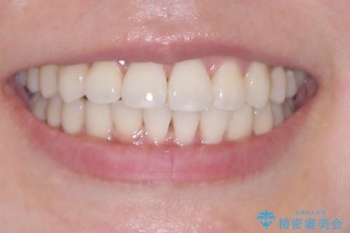

「歯並びと正中が整って、自信をもって笑えるようになった」

と大変ご満足のお言葉をいただきました。